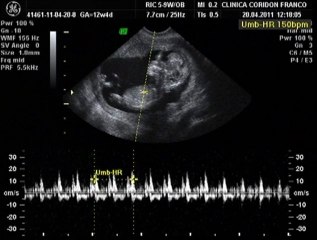

Malaga - 7 semanas pura y simplemente increíble